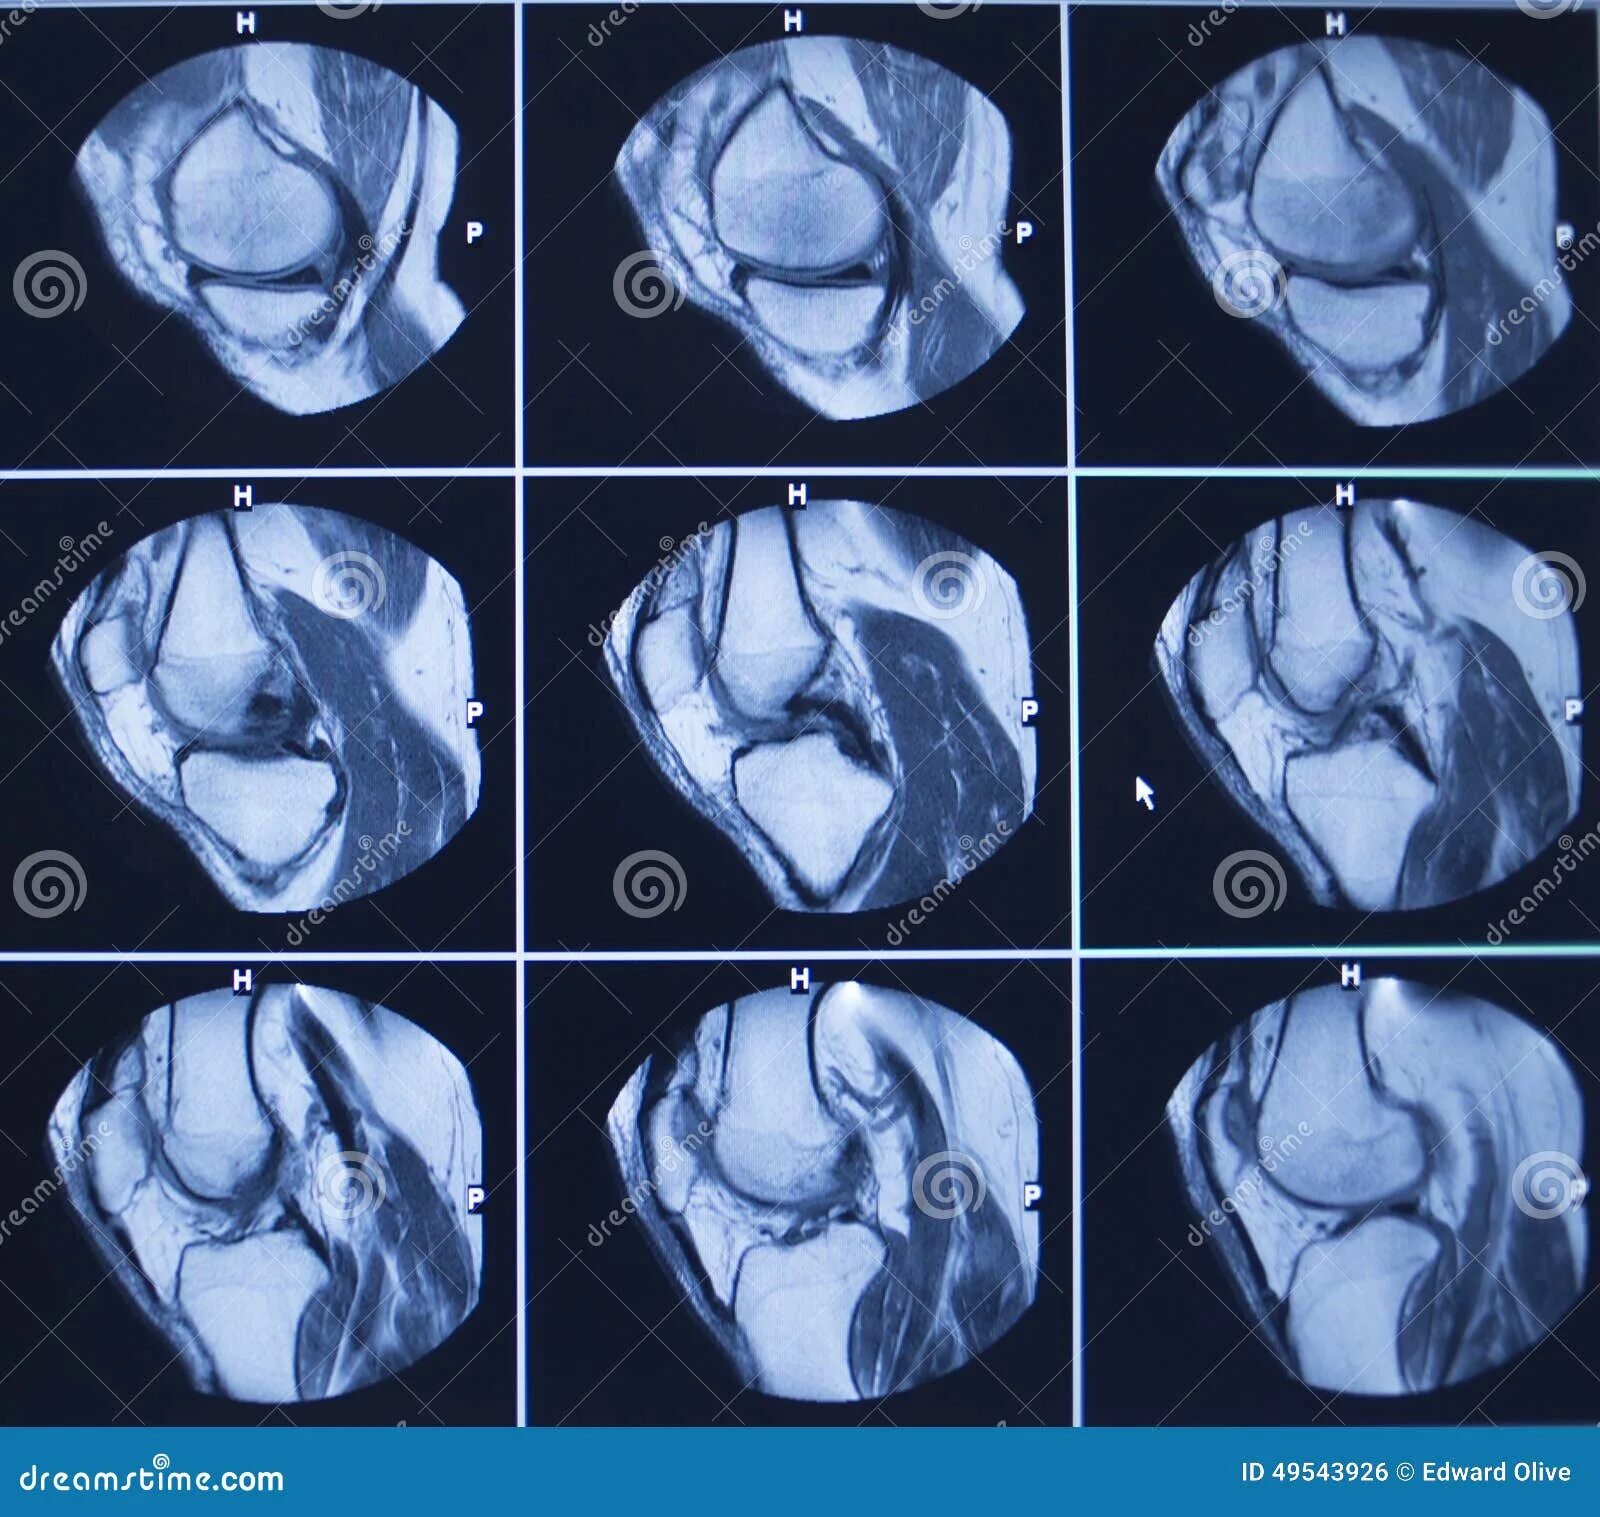

Повреждение мениска мрт